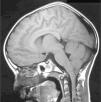

Se realizó una gammagrafía ósea de pelvis y MMII (fig. 1) sin alteraciones en caderas, mostrando menor captación derecha. Ante la sospecha de un proceso con afectación crónica del lado derecho, se realizó resonancia magnética cerebral y medular (figs. 2 y 3) y se diagnosticó de malformación de Arnold-Chiari tipo 1 (MCI) y siringomielia extendida hasta T8. El paciente fue derivado para intervención neuroquirúrgica que resultó exitosa.